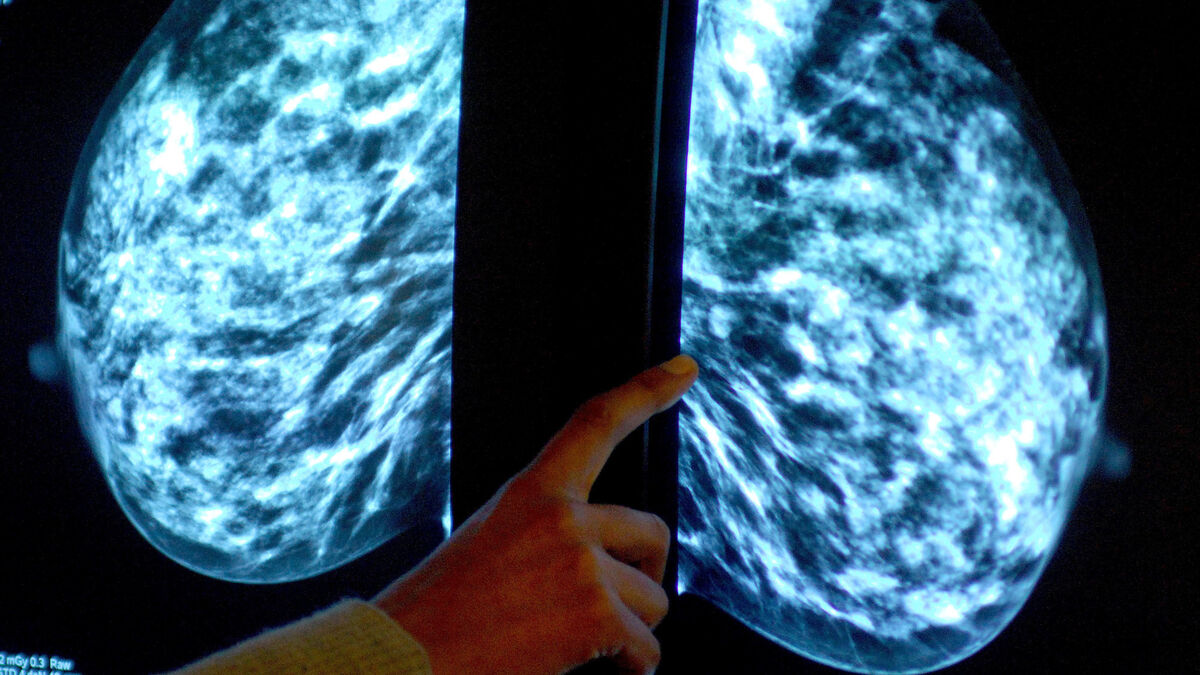

Woman's central claim was that a pea-sized/15mm lump assessed in May was cancer, rather than a cyst, and she should have been referred for further investigations that would have detected her cancer at that point.

Catriona Crumlish, who recovered following invasive treatments, alleged in her appeal that the High Court ignored key evidence that established her tumour diagnosed in October 2017 had been detectable when she first attended Letterkenny University Hospital five months earlier.